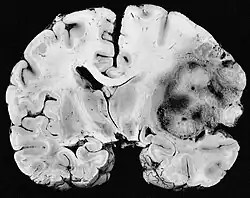

Um sarcoma é um cancro (câncer)/neoplasia que atinge células da mesoderme, em contraste com os cânceres mais comuns, que atingem a parte mais superficial ou interna do tecido. Pode atingir osso, cartilagem, gordura, músculo, vasos sanguíneos, ou tecidos moles. O termo advém do termo grego e significa "crescimento carnoso". São os tipos de câncer que mais fazem metástase e portanto os mais perigosos e difíceis de serem tratados. [1]

Sarcomas de baixa gravidade são geralmente tratados cirurgicamente, sem necessariamente precisar de radioterapia ou a quimioterapia, mas elas possam ser usadas dependendo do caso. Sarcomas de grau intermediário e grau alto são mais frequentemente tratados com uma combinação de cirurgia, quimioterapia e radioterapia, pois tumores de grau mais elevado são mais propensos a sofrer metástase, então precisam ser tratados de forma mais agressiva.[3] O reconhecimento de que muitos sarcomas são sensíveis à quimioterapia melhorou drasticamente a sobrevida dos pacientes. Por exemplo, na era antes da quimioterapia, a sobrevivência a longo prazo para pacientes com osteossarcoma localizado era apenas aproximadamente 20%, mas agora subiu para 60-70%.[4]